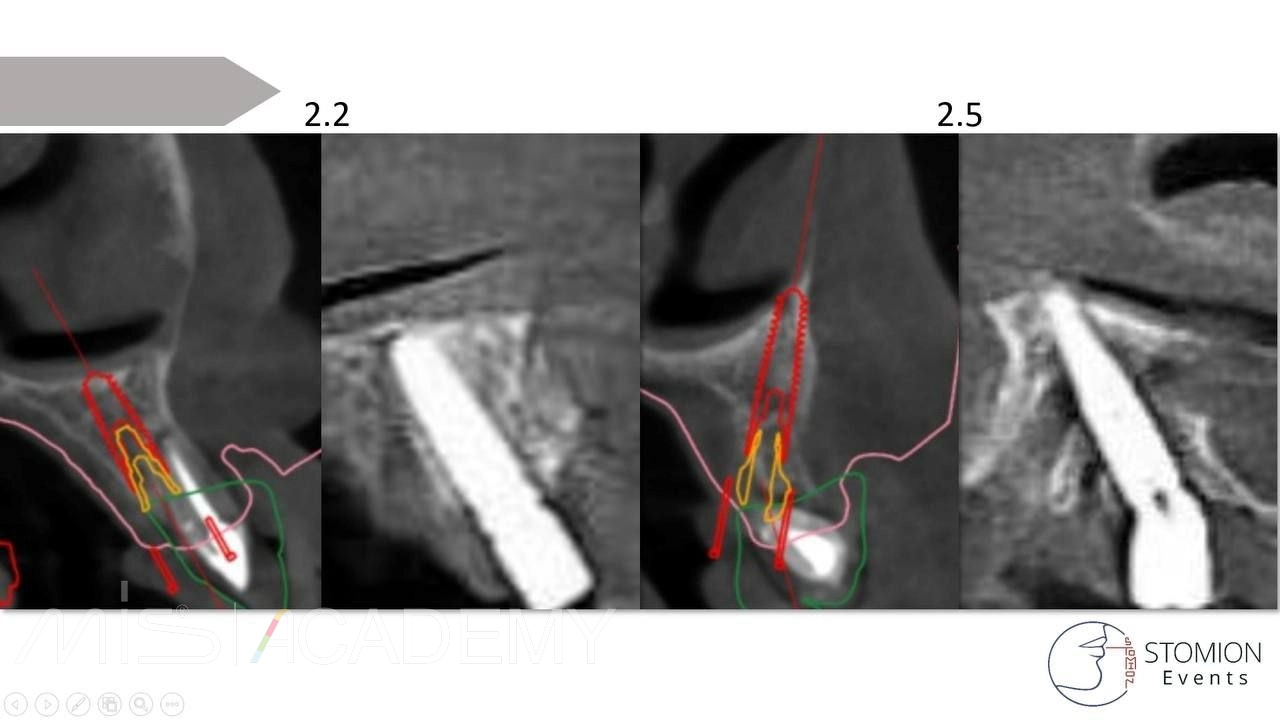

— На ВЧ так же Multifix на 4-х.

— MIS C1, коннекты во фронте, 30 градусов МЮ дистально.

— Навигация полнопротокольная, разборная, накостная.